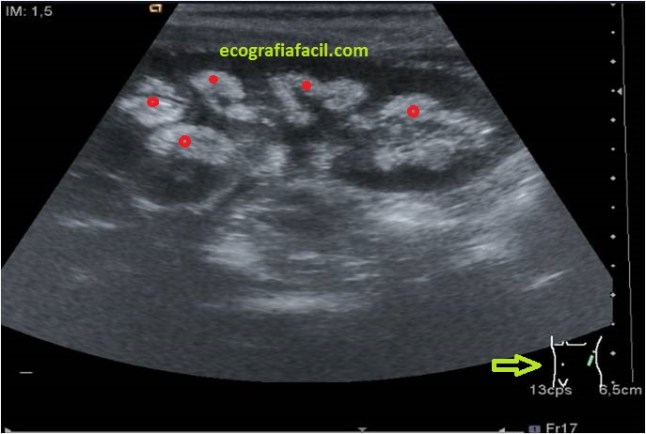

Vamos a ver unos riñones así en la ecografía:

En las imágenes superiores ves un corte longitudinal y otro axial del riñón.Marcado con círculos o flechas rojas, los pielones caliciales hiperecogénicos, muy llamativamente, indican patología a dicho nivel, la corteza renal, hipoecogénica y normal.

In the upper images you see a longitudinal and axial cut of the kidney. Marked with red circles or arrows, the hyperechoic calyceal skin, very strikingly, indicates pathology at this level, the renal cortex, hypoechoic and normal.